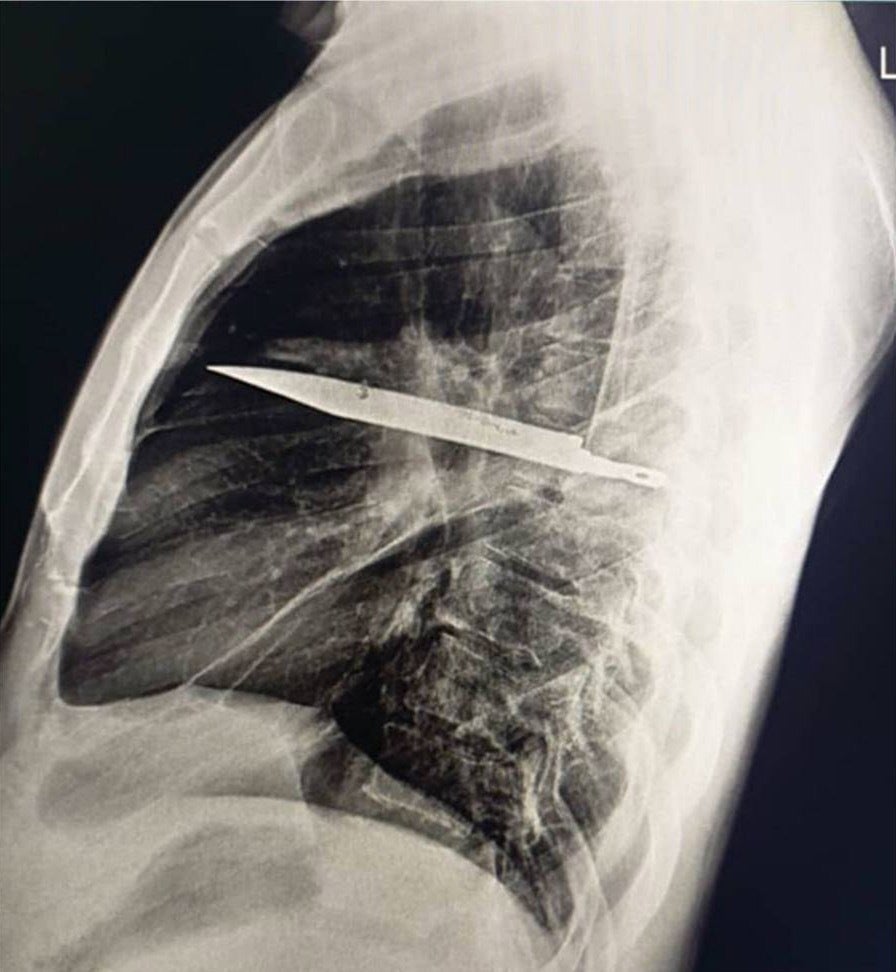

【閲覧注意】胸にナイフが刺さった状態のレントゲン写真

今回、レントゲン検査で胸部にナイフが残っているのが確認されたため直ちに手術が行われ、ナイフを抜去。男性は10日間後に退院しました。

報告は、「残存したナイフが致命的な状況につながる重大なリスクがあった」と述べています。